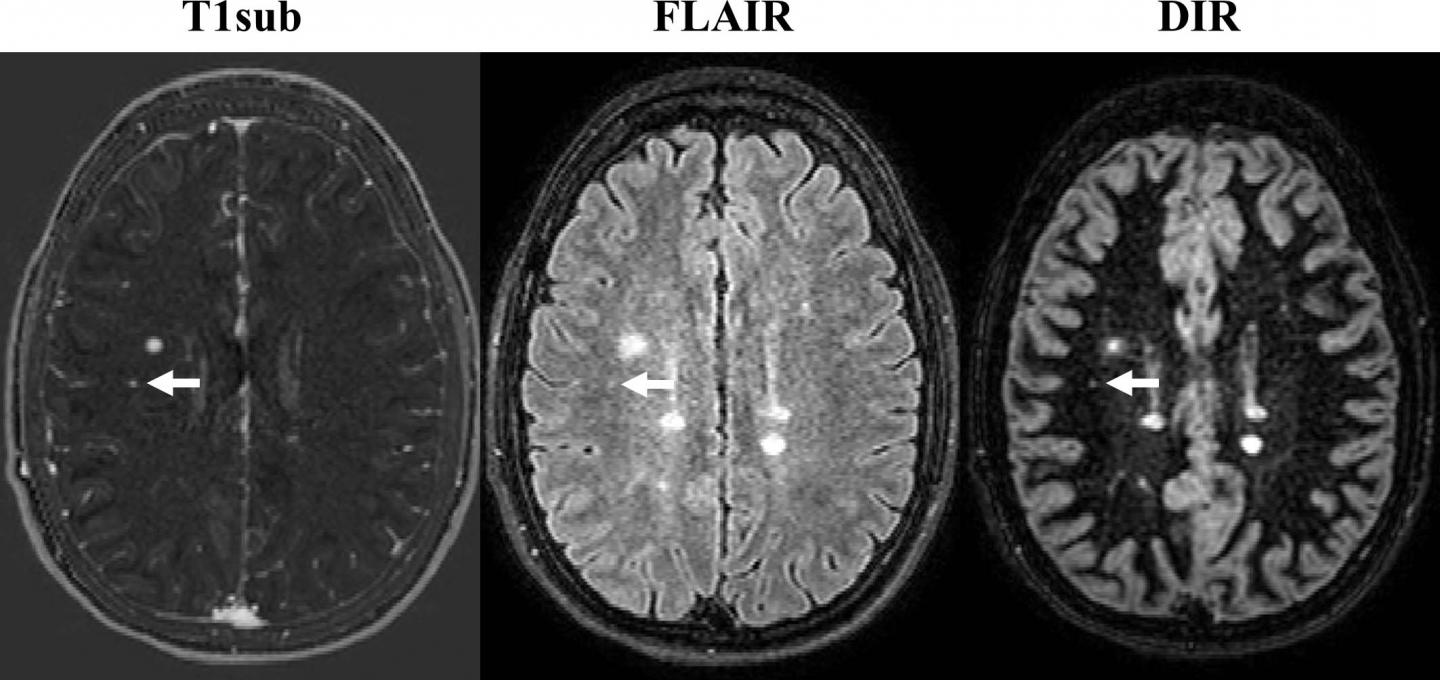

To learn more, Dr. Wiestler and colleagues used MRI to assess new or enlarged lesions in 359 patients with MS. Of 507 follow-up scans, 264 showed interval progression, defined by as at least one new or unequivocally enlarged lesion on follow-up MRI scans. There were a total of 1,992 new or enlarged lesions. With 3T MRI, the assessment of interval progression did not differ significantly between the contrast-enhanced and non-enhanced images.

"In over 500 follow-up scans, we missed only four of 1,992 new or enlarged lesions," Dr. Wiestler said. "Importantly, we did not miss disease activity in the non-enhanced scans in a single follow-up scan."

Dr. Wiestler credited an image subtraction pipeline developed and researched at his facility for the powerful sensitivity of the non-contrast MRI in detecting newly occurring lesions. The approach combines 3-D MRI and subtraction techniques, which cancel out unchanged areas in the follow-up image, substantially improving visualization of new or enlarging white matter lesions.

This combination of 3-D sequences and subtraction techniques is key to improving sensitivity for detecting newly occurred lesions, Dr. Wiestler said.